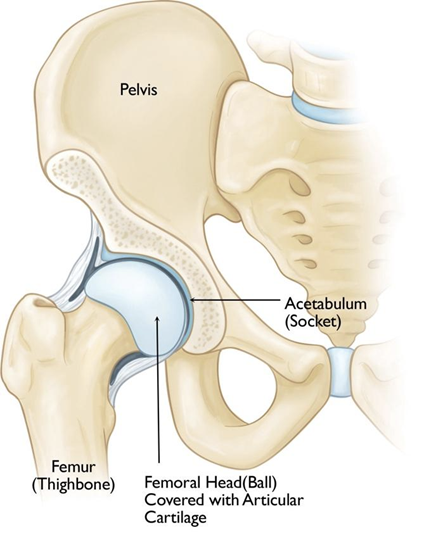

髋关节骨关节炎(OA)是一种退行性关节疾病,表现为髋关节软骨逐渐磨损。当保护性软骨消失后,骨骼直接摩擦,导致疼痛、僵硬和活动受限。全球数百万人受此困扰,尤其是老年人,生活质量显著下降。然而,保守治疗和再生医学的进步为缓解症状和延缓疾病进展提供了希望。本文探讨髋关节骨关节炎的病因、风险因素、发展阶段、传统及前沿治疗方式,包括何时需要全髋关节置换术等外科干预。

髋关节骨关节炎的病因

髋关节OA的发生与软骨逐渐磨损相关,主要原因包括:

- 原发性OA:与年龄相关的“磨损”,因关节长期重复受力。

- 继发性OA:由外伤(如骨折、脱位)、先天性异常(如髋关节发育不良)、炎症性疾病(如类风湿关节炎)或肥胖引发。